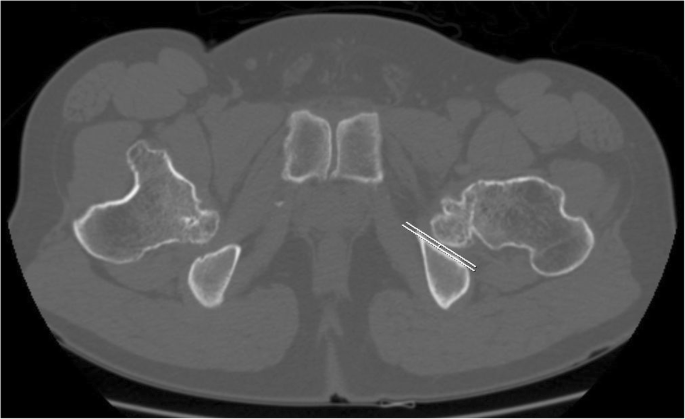

Radiographic analysis was conducted using the last follow-up radiographs in patients who had not undergone any surgical intervention, and the last preoperative radiographs in those who had undergone surgical treatment around the hip joints. For the morphometry of the hip joint in patients with MHE, the femoral neck-shaft angle of Muller [19] was evaluated to assess proximal femur deformity, and Sharp’s acetabular angle [20] and the center-edge (CE) angle [21, 22] were evaluated to assess the deformities of acetabulum (Fig. 2). For FAI evaluation, alpha angle (Fig. 2) of all hips was measured regardless of the presence or absence of symptoms. For IFI evaluation, hip CT studies in patients with MHE were performed in the neutral supine position and the nearest distance between the exostoses and ischium around the lesser trochanter area were measured at axial plane (Fig. 3).

Eighteen of 102 MHE hips (17.7%) presented IFI symptom in this study. As a result of comparing and analyzing the morphometric studies of the IFI symptom and non-IFI symptom group, the IFI symptom group showed a similar deformity pattern compared to the study conducted between the FAI and non-FAI symptom groups. IFI symptom group showed the more coxa valga deformity (IFI-symptom group: 150.9° (range, 138.4° - 161.1°); non IFI-symptom group: 142.7° (range, 127.9° - 166.3°); P < 0.001), more tendency of acetabular dysplasia measured by Sharp’s angle (IFI-symptom group: 44.7° (range, 31.5° - 60.5°); non IFI-symptom group: 41.4° (range, 34.0° - 53.6°); P = 0.013) and CE angle (IFI-symptom group: 21.1° (range, 4.0° - 40.2°); non IFI-symptom group: 29.3° (range, 9.3° - 41.1°); P = 0.002), and more increased alpha angle (IFI-symptom group: 73.3° (range, 56.0° - 88.4°); non IFI-symptom group: 56.8° (range, 38.3° - 83.4°); P < 0.001) compared to that of the non IFI symptom group. Measured values to evaluate the deformities between the IFI and non IFI symptom group showed significant difference as noted in Table 2. For further study between the IFI and non IFI-symptom group, total 52 MHE hips being conducted hip CT including 18 MHE hips who had confirmed as having IFI symptom in physical examination were evaluated. In a further comparison between the IFI symptom and non IFI symptom group who underwent CT evaluation, the minimum ischio-femoral distance of the IFI-symptom group showed more decreased value with a mean value of 6.7 mm (range, 2.5–9.8) than that of non IFI-symptom group with a mean value of 16.4 mm (range, 10.2–25.2), and a significant difference (P < .001) was found (Table 3). In addition, minimum ischio-femoral distance was found to have a statistically significant reverse relations with the coxa valga deformity (P = 0.002), and as a result, it was confirmed that the minimum ischio-femoral distance decreased as the coxa valga deformity increased.